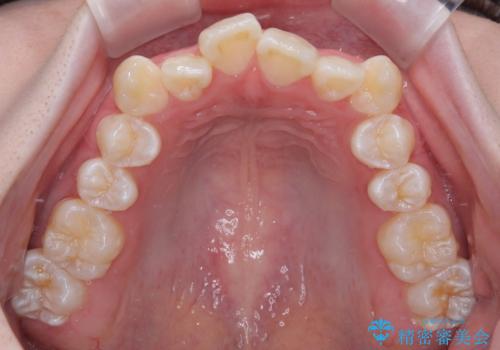

- 「前歯のデコボコ(叢生)をきれいに整えたい」とのことでご来院されました。

マウスピース矯正も検討されていましたが、「装着時間の自己管理が難しそう」「なるべく早く治療を終えたい」とのご希望から、ワイヤー矯正を選択されました。

目立ちにくさと費用のバランスを考慮し、プラスチックブラケット+メタルワイヤーを採用。日常生活でも装置の存在感を気にせずお過ごしいただけます。